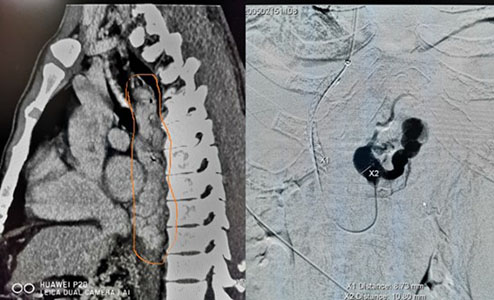

五一劳动节当天,湘雅三医院急诊科抢救室收治一名肝硬化门静脉高压患者,患者近三日有上消化道出血表现。急诊CT检查图像显示,患者肝硬化非常严重,门静脉明显增粗,且胃底、胸部食管粘膜下可见大量增粗、曲张的静脉,伴有腹水。考虑到患者近几日有上消化道出血,影像检查显示胃底、食管粘膜下有大量曲张的静脉,患者随时面临再次致命性大出血的危险。放射科主任容鹏飞、王维教授在仔细分析患者病情后指示,食管、胃底粘膜下大量曲张的静脉犹如一颗颗“炸弹”、随时会引爆导致致命性大出血,应尽快给患者实施经颈静脉肝内门体分流术(TIPS)。考虑到患者病程时间长、门脉高压程度严重,放射介入团队在完善患者术前检查、评估后,5月2日由叶斌、张声旺、吴作为、梁友发、黎姿团队成功为其实施TIPS手术,顺利拆除了食管、胃底粘膜下的一颗颗“炸弹”。目前患者恢复良好,已经开始进食流质,腹胀逐渐缓解、腹围逐渐缩小,患者及家属表示感谢。

经颈静脉肝内门体分流术(TIPS)是指经颈静脉入路从肝静脉穿刺肝内门静脉,在肝静脉与门静脉之间建立支架分流道,以达到降低门静脉压力的作用,是治疗门静脉高压引起的消化道出血、顽固性腹水等并发症的微创治疗技术。该技术具有手术时间短、创伤小、术后患者康复快的特点。中南大学湘雅三医院影像医学与核医学学科带头人王维教授于上世纪九十年代率先在湖南省内开展TIPS手术。TIPS手术是高难度、高风险性的介入手术,由于该科在关键的术前评估和术中门静脉定位技术有其独特之处,是目前湖南省三甲医院中TIPS手术唯一“零”严重并发症的医院。容鹏飞强调,针对病情危急、难以耐受外科治疗的门静脉高压消化道出血患者,放射介入团队可以实施挽救性、早期TIPS手术,达到精准、快速治疗消化道出血的目的。